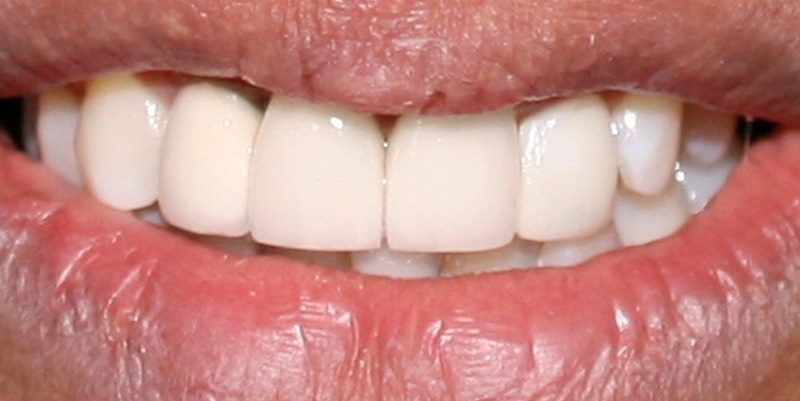

Caso Clínico Antes

Caso Clínico Después